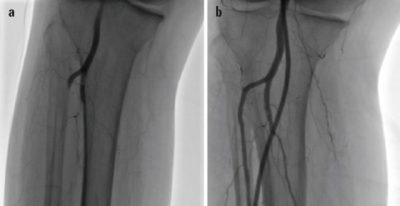

يستخدم دواد خاص جدا لقدرته علي اذابه الجلطه الشريانيه اذا كانت حديثه أي لم يمر عليها اكثر من أسبوعين

يتم حقن دواء الاذابه من خلال القسطره الطرفيه

ويمكن مزجه بتقنيه اخري من وسائل العلاج